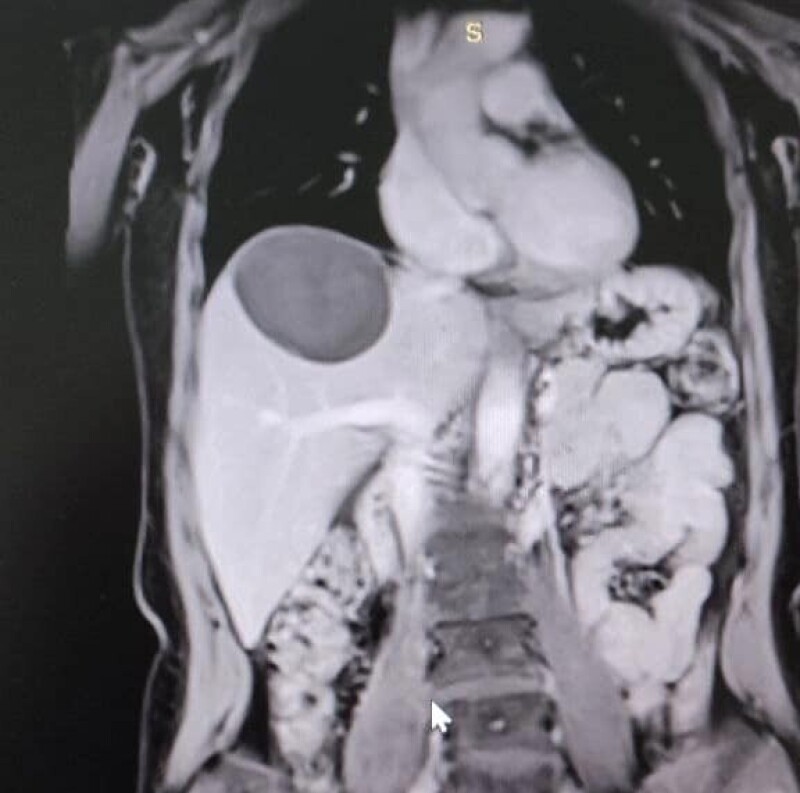

50-річна жінка зі скаргами на тиснення і біль у правому підребер’ї поступила у Володимирське ТМО. У неї діагностували небезпечне захворювання - ехінококову кісту, яку хірургічно видалили.

Паразитарна кіста в печінці нагадує навколоплідний міхур, всередині якого дозрівають личинки ехінокока. Новоутворення поступово зростає і часом досягає гігантських розмірів (до 50 см у діаметрі).